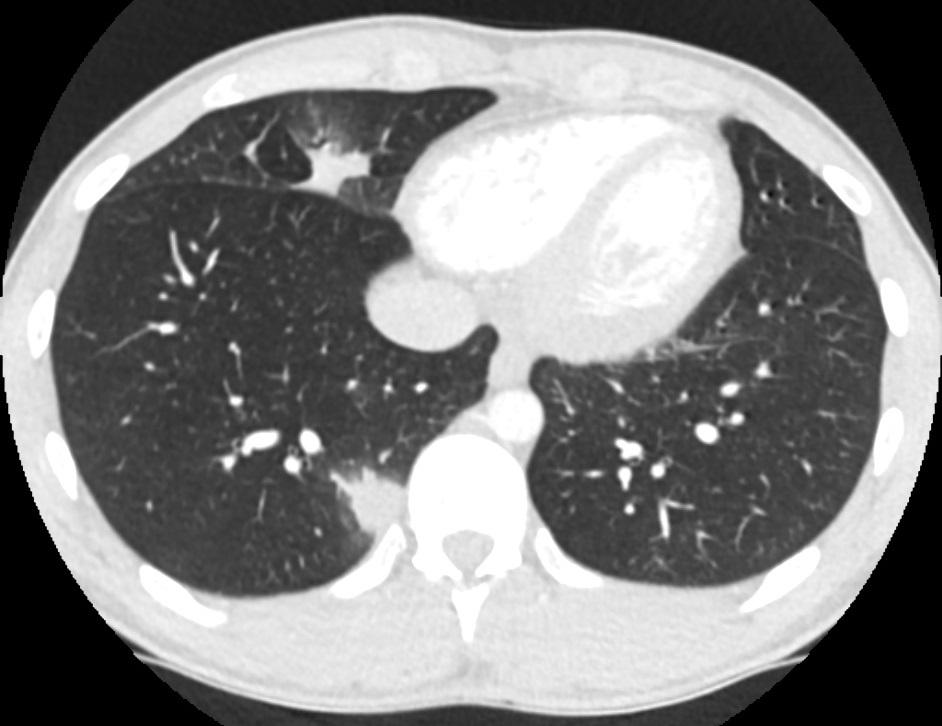

Gepubliceerd: Week 39 - 2018 242 deelnemers Een 25-jarige man komt op de SEH met thoracale pijn die vastzit aan de ademhaling. Ook hoest hij wit, bloederig sputum op. Recentelijk heeft hij door Zuid-Amerika gereisd. Wat is uw diagnose? Antwoord multipele longinfarcten coccidioidomycosis pulmonale histoplasmose angio-invasieve aspergillose Antwoord controleren